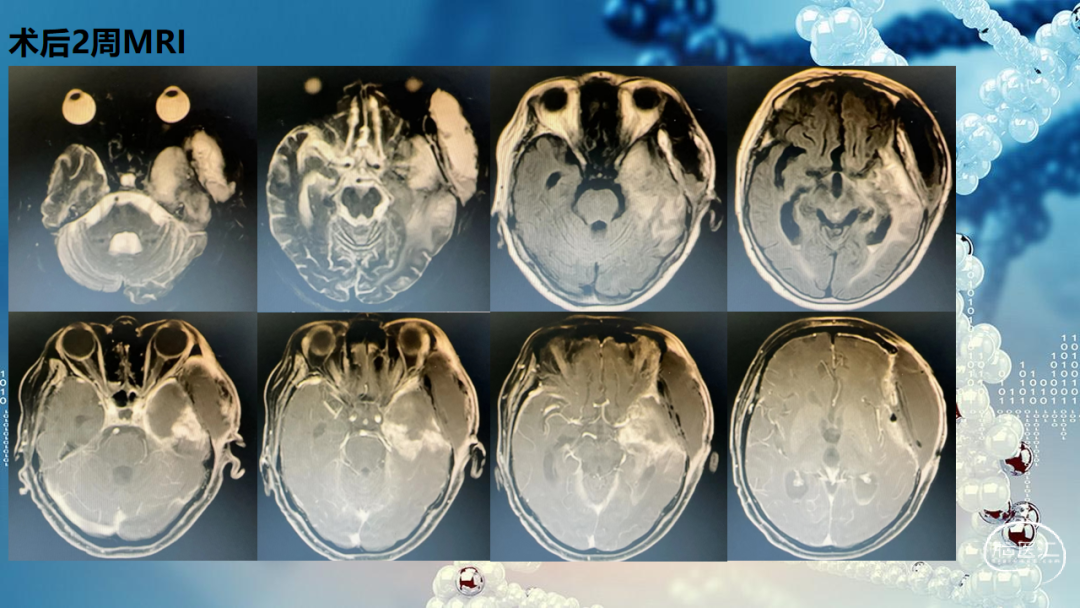

贵州医科大学附属医院暨肿瘤医院肿瘤科:考虑该病例病灶范围大,术后残留靠近颞叶海马及脑干,术后CT融合MRI勾画放疗靶区,放疗靶区GTV包含术腔、增强残留病灶、T2flair异常信号区域,给与剂量60Gy,外扩2cm时考虑脑干,脑干附近缩回0.5cm,给予50Gy剂量,术后标准化疗。该病例术后至复发共22月,复发后由于颅内压高致昏迷进行急诊手术,术后院GOSIV级,已出院,二次术后未进行再次放疗,考虑第一次放疗剂量较大且靠近脑干以及十二周期化疗,所以可以先用药物治疗,比如贝伐单抗联合化疗,以及免疫治疗。

华西医院神经外科:该病例总体来讲治疗效果不错,IDH野生型的胶质母细胞瘤4级第一次术后达到22月,复发后再次手术,从手术角度提出两点建议,第一是切除程度,手术将强化病灶切除的不错,病灶位于左颞海马,如果在功能监测下积极点可以再多切一些;第二是对于胶质瘤手术不建议去骨瓣减压,术中切除病灶后可以充分减压,骨瓣复位有助于后期综合治疗,现在的外科技术完全能够有效的进行病灶切除及彻底的止血,不需要预防去骨瓣减压。

华西医院病理科:本例病理诊断明确。第一次是非常典型的胶质母细胞瘤,形态学细胞密度高,可见大量栅栏状坏死,TERT启动子突变,胶质母细胞瘤的诊断非常明确。复发后形态学朝肉瘤方向发展,呈胶质肉瘤形态,大范围还是属于胶质母细胞瘤,预后会更差一些。

华西医院肿瘤科:对于该病例是否再次放疗的问题同意金书记和李主任的意见。该病例第一次术后放疗范围很大,照射剂量60Gy,放疗时间不到2年,再程放疗的放射性坏死概率非常高。第二次术后如果影像学全切,建议使用电场加化疗,可与患者沟通,尝试加用免疫治疗;该病例目前未见明显水肿及占位效应,建议暂缓使用贝伐珠单抗;若第二次术后有小部分残留,建议可以伽马刀治疗。

华西医院神经外科:该病例的治疗是综合治疗的成果,因为该病例有MGMT甲基化,可以使用替莫唑胺剂量密度方案。